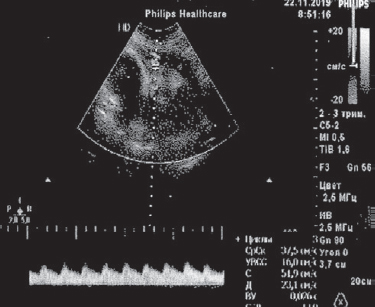

Однако к 32 нед. беременности у пациентки вновь было отмечено некоторое усиление воспалительного ответа организма (с возрастанием показателя ЛИИ до 2,5 усл. ед.) с одновременным снижением АИ до 9 мм (рис. 4).

Рис. 4. Данные ультразвукового исследования через 56 дней после отхождения вод (22.11.2019), амниотический индекс 9 мм